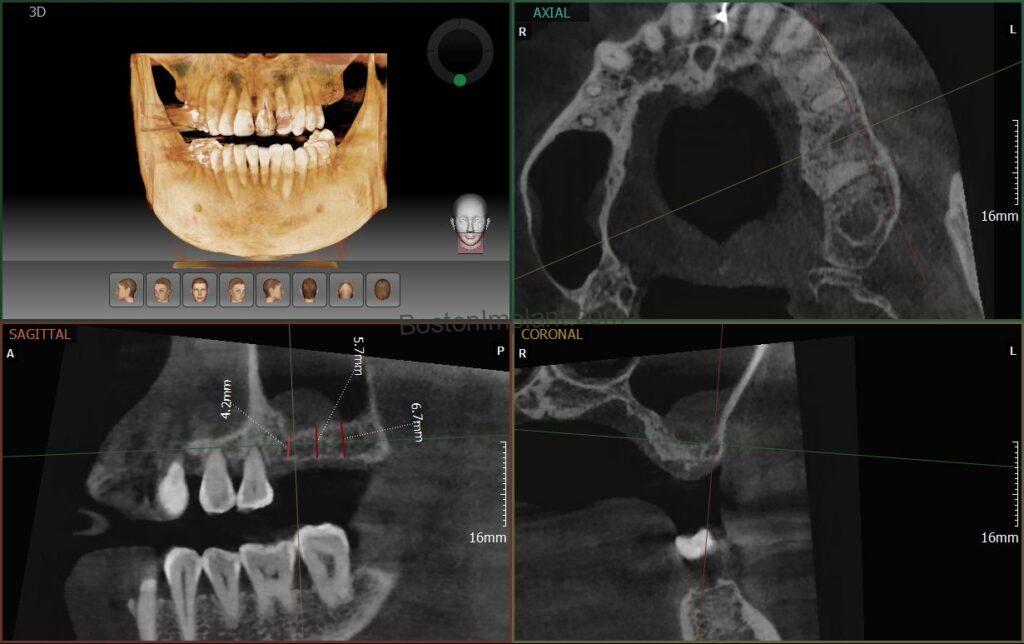

To assess his bone structure, we performed a CBCT (Cone Beam Computed Tomography) scan, a detailed 3D X-ray. Regrettably, he had insufficient bone in both upper molar areas, necessitating bilateral sinus lifts. (For more on sinus lifts information, please check this post).

Following a thorough consultation, we developed a comprehensive treatment plan, including five implants, bilateral sinus lifts, and other general dental procedures. We utilized a surgical guide for precise implant placement. (More information on surgical guides can be found here ).